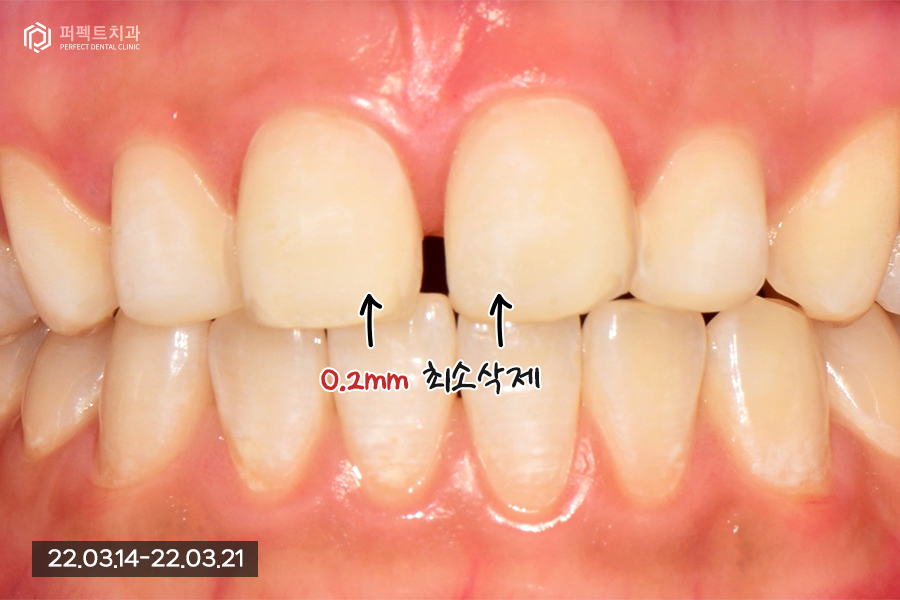

치아를 삭제한 후의 사진인데요. 두번째, 세번째 치아들은 뒤로 들어가있고 앞니가 튀어나온 상태이기 때문에 삭제할 필요가 없었습니다.

환자분은 아까 말씀드린 것처럼 앞니가 튀어나와 보여도 괜찮으니 최소삭제를 원하셨기 때문에 앞니는 0.2mm정도 최소삭제, 나머지 치아들은 0.1mm이내로 다듬기만 하였습니다.